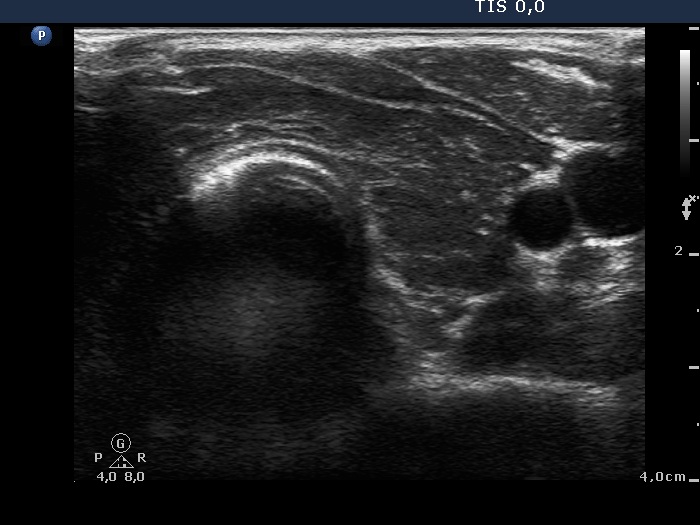

Follow-up examination 15 months after first visit (third row of images):

Clinical presentation: The patient was regularly followed-up and was euthyroid on daily 10 mg methimazole. She had no complaints.

Palpation: no abnormality.

Results of blood test: euthyroidism on daily 10 mg methimazole (TSH 1.83 mIU/L, FT4 14.6 pM/L).

Ultrasonography: The thyroid was echonormal and contained small hypoechogenic areas. The vascularization was practically absent.

The thyrostatic was discontinued.